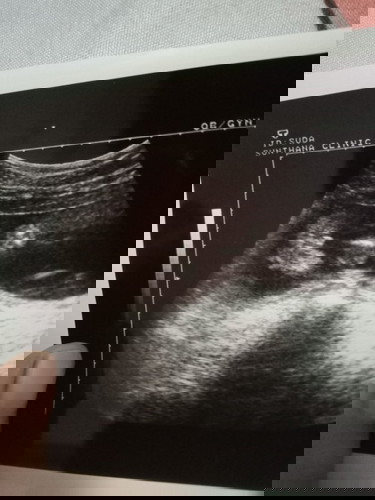

ช่วยดูหน่อยค่ะใช้เพศหญิงจริงไหม😊

คล้าย ญ. ค่ะ ไม่มียื่นๆ 😆

หมอว่าเป็นผู้หญิงคะหมอว่ามาเป็นกลีบเลย555